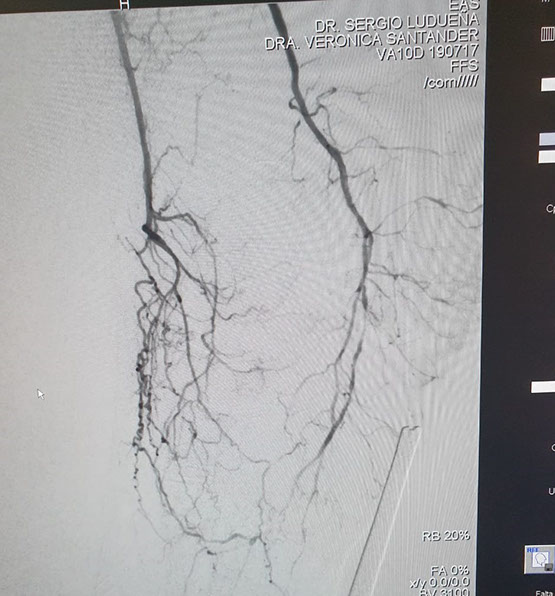

El Dr Sergio Raul Ludueña Jefe del Servicio de Hemodinamia de INCOR nos comentó sobre procedimiento realizado en el día de ayer en en el Servicio. "Queremos compartir con ustedes si bien no es un caso coronario , es un paciente obeso mórbido, diabético, con amputación supracondilea de miembro inferior izquierdo hace 3 años y actualmente con isquemia critica de miembro inferior derecho, con oclusión de ambas tíbiales y sin circulación en el pie".

Se realizó un abordaje híbrido con el Dr. Alejandro Flores, y se re canalizó ambas arterias tíbiales. Procedimiento inédito en nuestra provincia.

Las imágenes siguientes son previas al procedimiento y posterior se ve ambas arterias tíbiales permeables, y circulación en el pie